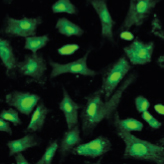

연골 보호 및 재생

항염증, 통증 제거

연골 보호